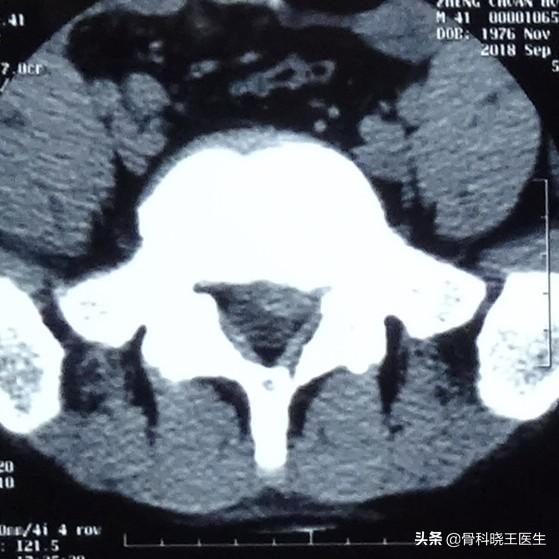

多くの患者や友人は、腰椎椎間板ヘルニアは自然に元に戻るのだろうか?実際、腰椎椎間板が一度突出すると、元に戻ることは非常に難しく、それは腰椎椎間板の構造によって決まります。腰椎椎間板は、人体の隣り合う2つの腰椎の間にあり、外側の線維輪と真ん中の髄核から構成されています。 腰椎椎間板ヘルニアとは、髄核が周囲の線維輪を突き破って外側に突出することを意味します。従って、腰椎椎間板ヘルニアが発生するということは、腰椎椎間板周囲の線維輪構造が損傷したということであり、線維輪は絡み合って複雑な構造をしており、血流もなく治癒力も乏しく、一度破壊されると元の状態に戻すことは不可能で、瘢痕化してかろうじて治ったとしても、強度はかなり悪くなります。椎間板ヘルニアは、髄核が完全に環状線維を突き破らなければ、骨操作や牽引によって部分的に引っ込めることは可能ですが、体重をかけても髄核が突出し続ける限り、長期間引っ込んだ状態を維持できる可能性はほとんどありません。 また、環状線維は何層にも分かれているため、すでに違う層の環状線維に髄核が詰まっていることもあり、これも引っ込むことは困難です。したがって、いかにして髄核を引っ込めるかを考えるのではなく、いかにしてヘルニアを悪化させないかを考えるべきなのです。

前述したように、腰椎椎間板ヘルニアはなかなか元に戻らないので、治療後に腰痛や足の痛みが出ないのはなぜでしょうか?実は腰痛や下肢痛につながる腰椎椎間板ヘルニアの原因は非常に複雑で、神経の圧迫はその一部に過ぎません。腰椎椎間板ヘルニアは、腰椎のゆるみ、不安定性、腰椎の筋肉の緊張を生じさせると同時に、ヘルニア自体が炎症性刺激につながることが腰痛の主な原因です。脚の痛みの原因は、ヘルニアによる神経の圧迫だけでなく、椎間板変性の過程で「神経根皮炎の化学的刺激」によって炎症性物質が放出されたり、髄核が体を刺激して「自己免疫性神経原性」、つまり「自己免疫性」を生じさせたりすることもあります。また、椎間板変性時に放出される炎症性物質による「化学的刺激性神経根炎」や、髄核が身体を刺激することによる「自己免疫性神経根炎」の場合もある。そのため、腰椎椎間板ヘルニアの足腰があまり痛くないということは、病気が良くなっていること、正しい方法で治療していることを示しますが、「ヘルニア」の回復を意味するものではありません。

実際、道行く人を無作為に選んで腰椎CTを撮ると、多くの人が腰椎椎間板ヘルニアを持っていますが、その大半は不快な症状もなく、普通の人と変わらない社会生活を送っています。したがって、椎間板ヘルニアと診断されても、ヘルニアが回復するのか、症状が悪化するのか、あまり心配する必要はありません。ほとんどの場合、椎間板ヘルニアの症状は保存的治療ですぐに軽快しますし、何年も、あるいは10年以上も症状が再燃しないこともあります。クリニックでは、医師は症状を緩和するために腰椎を保護する様々な方法も提案し、この面から腰椎椎間板ヘルニアを治すことができます。